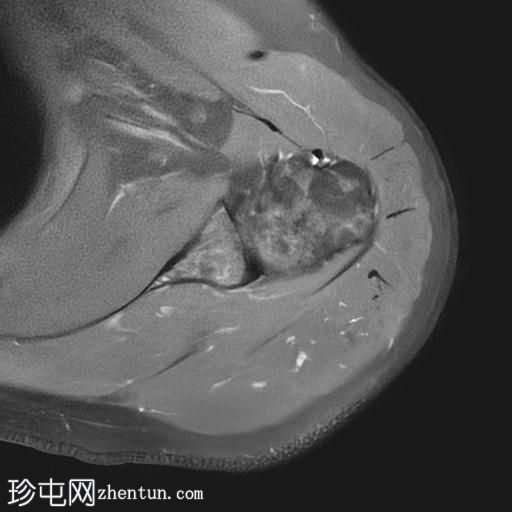

MRI

轴位PD序列

脂肪抑制序列

冠状位

T2加权像

T1加权像

冠状位PD序列

矢状位

PD脂肪抑制序列

冈上肌腱中后部关键区及肌腱止点纤维可见一低信号椭圆形病灶,大小约5 x 8 x 16 mm,提示钙化性肌腱炎。

肩锁关节轻度关节囊肥厚及退行性改变。

肩峰类型:II型

肩袖钙化性肌腱炎是一种自限性疾病,由羟基磷灰石钙沉积引起,最常见于冈上肌腱。